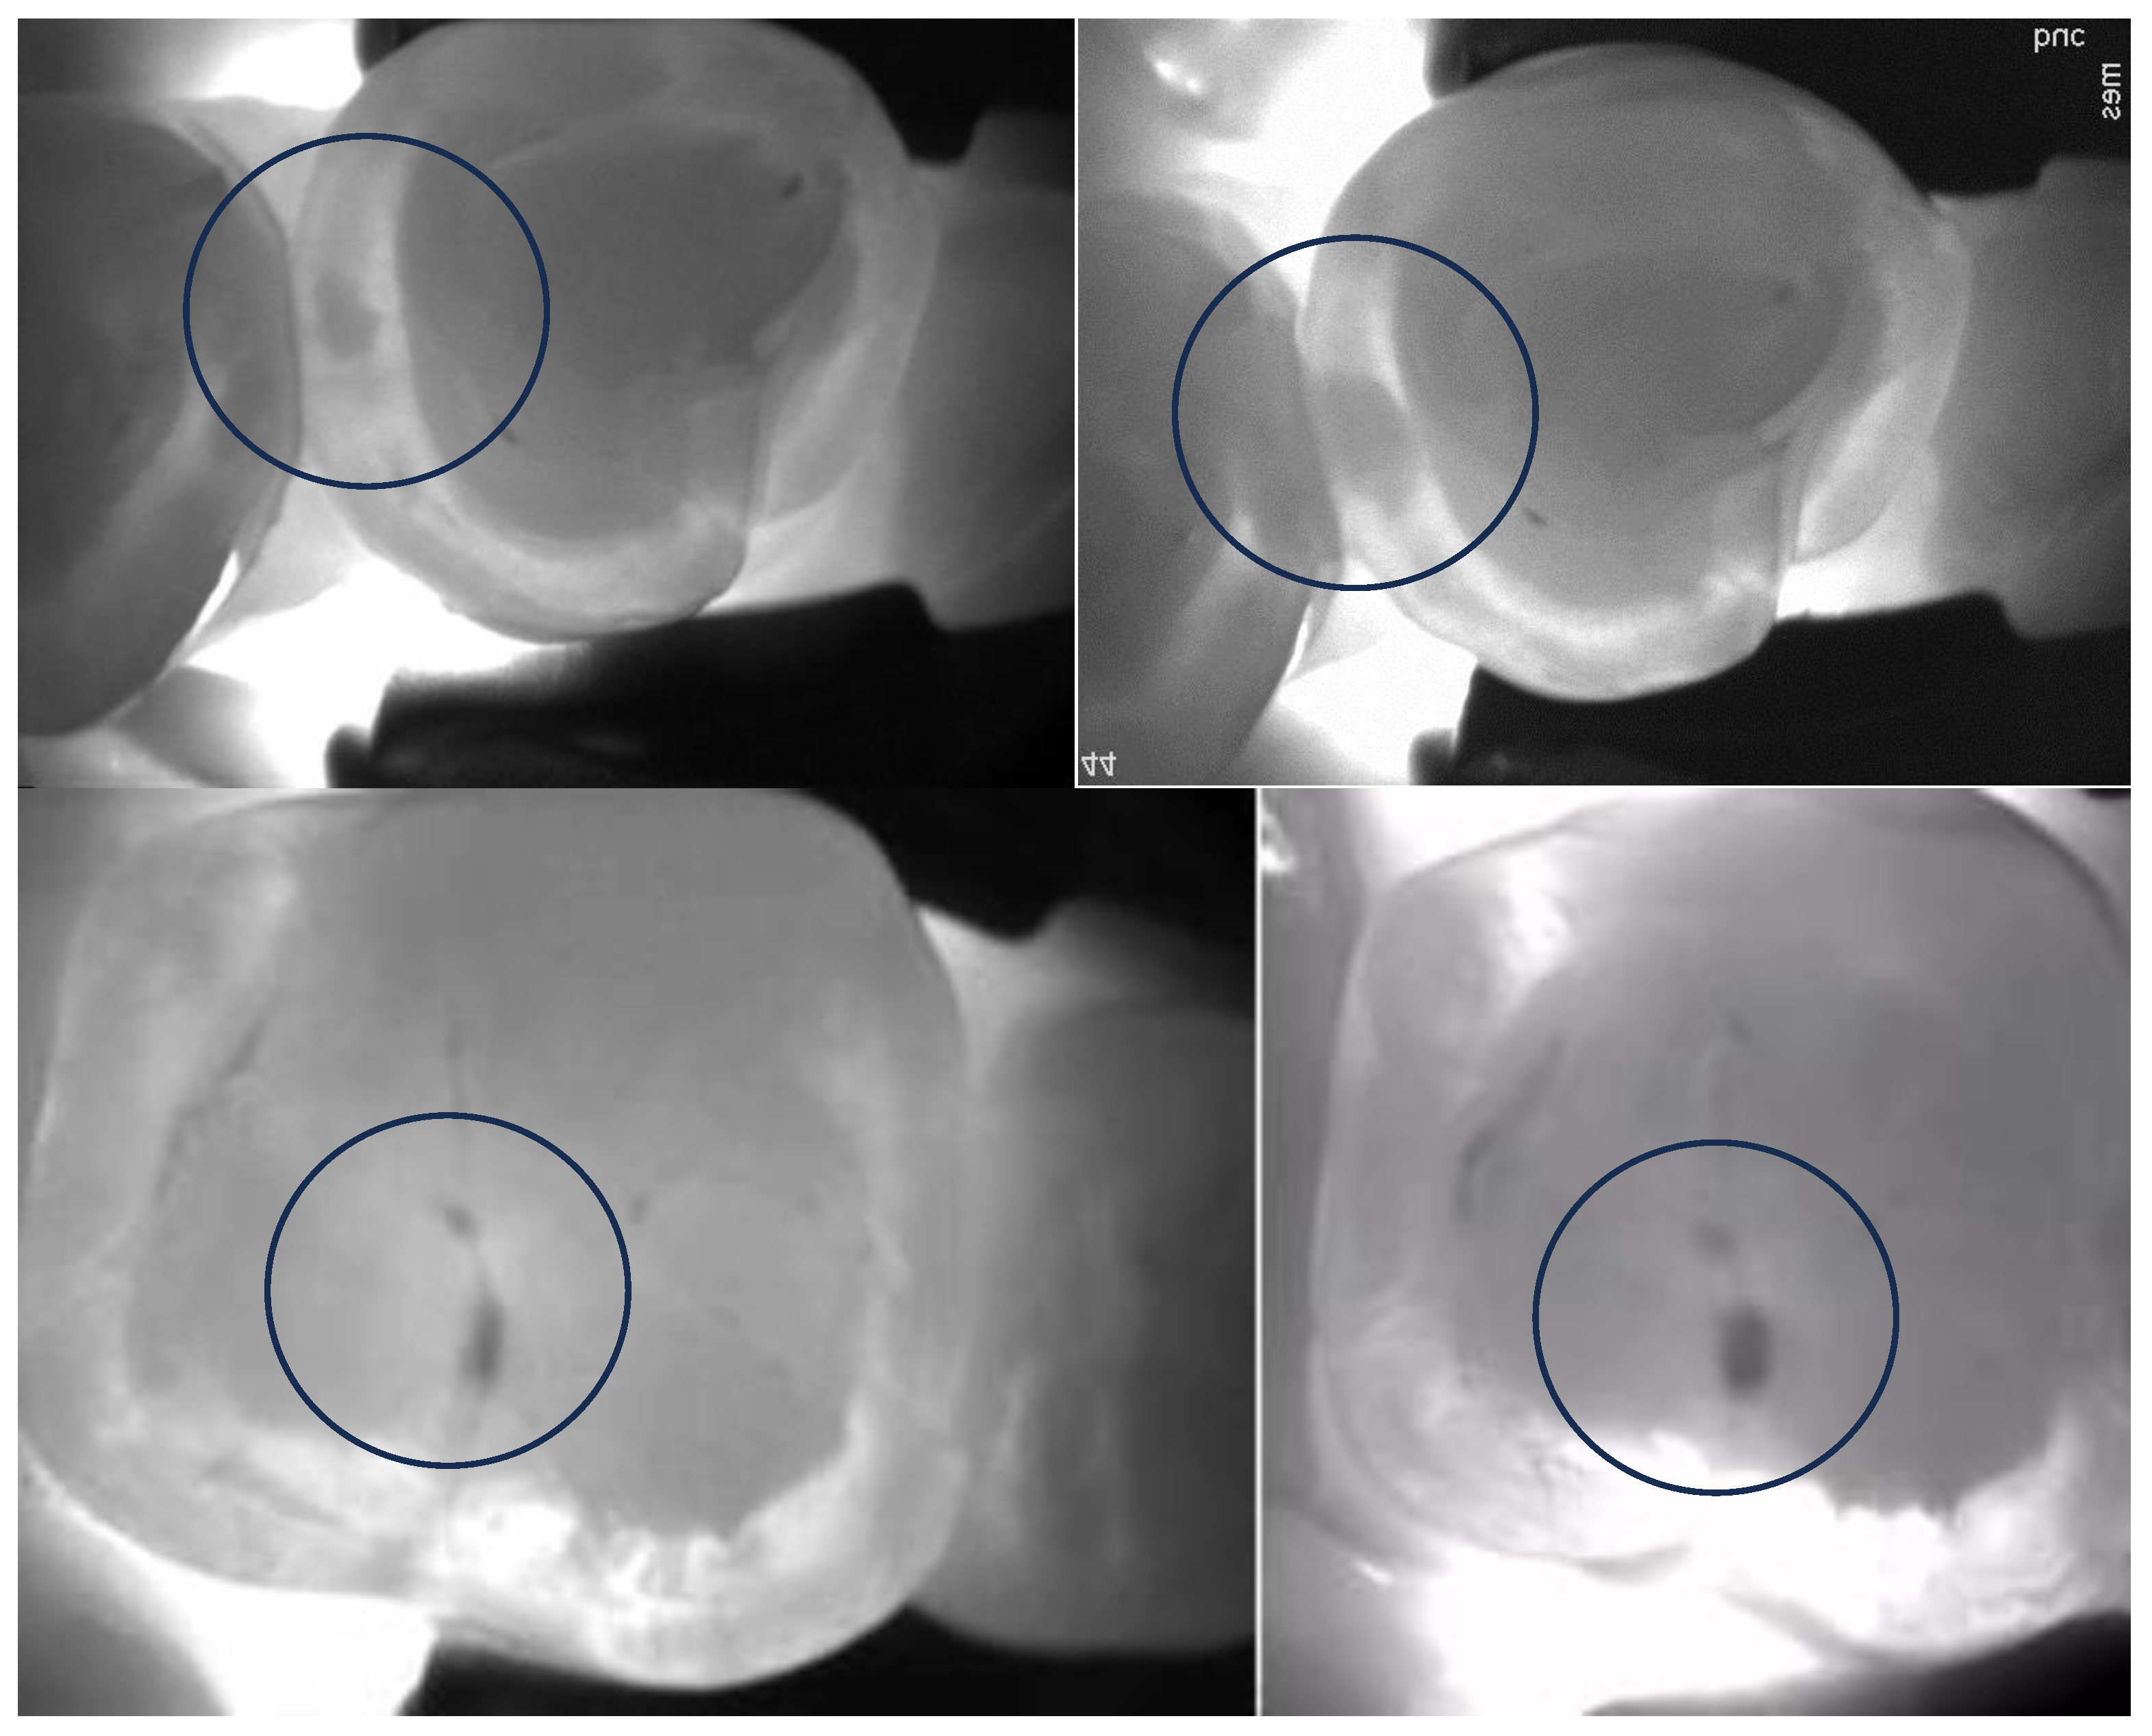

4.1.2. The Use of Near-Infrared Transillumination in Caries Detection and Monitoring

- Mohamed Nur, M.; Vazquez, L.; Anton, Y.O.C.; Giacobino, C.; Krejci, I.; Abdelaziz, M. Near-Infrared Transillumination for Occlusal Carious Lesion Detection: A Retrospective Reliability Study. Diagnostics 2022, 13, 36. [Google Scholar] [CrossRef]

- Abdelaziz, M.; Krejci, I. DIAGNOcam—A Near Infrared Digital Imaging Transillumination (NIDIT) technology. Int. J. Esthet. Dent. 2015, 10, 158–165. [Google Scholar] [PubMed]

- Sochtig, F.; Hickel, R.; Kuhnisch, J. Caries detection and diagnostics with near-infrared light transillumination: Clinical experiences. Quintessence Int. 2014, 45, 531–538. [Google Scholar] [CrossRef] [PubMed]